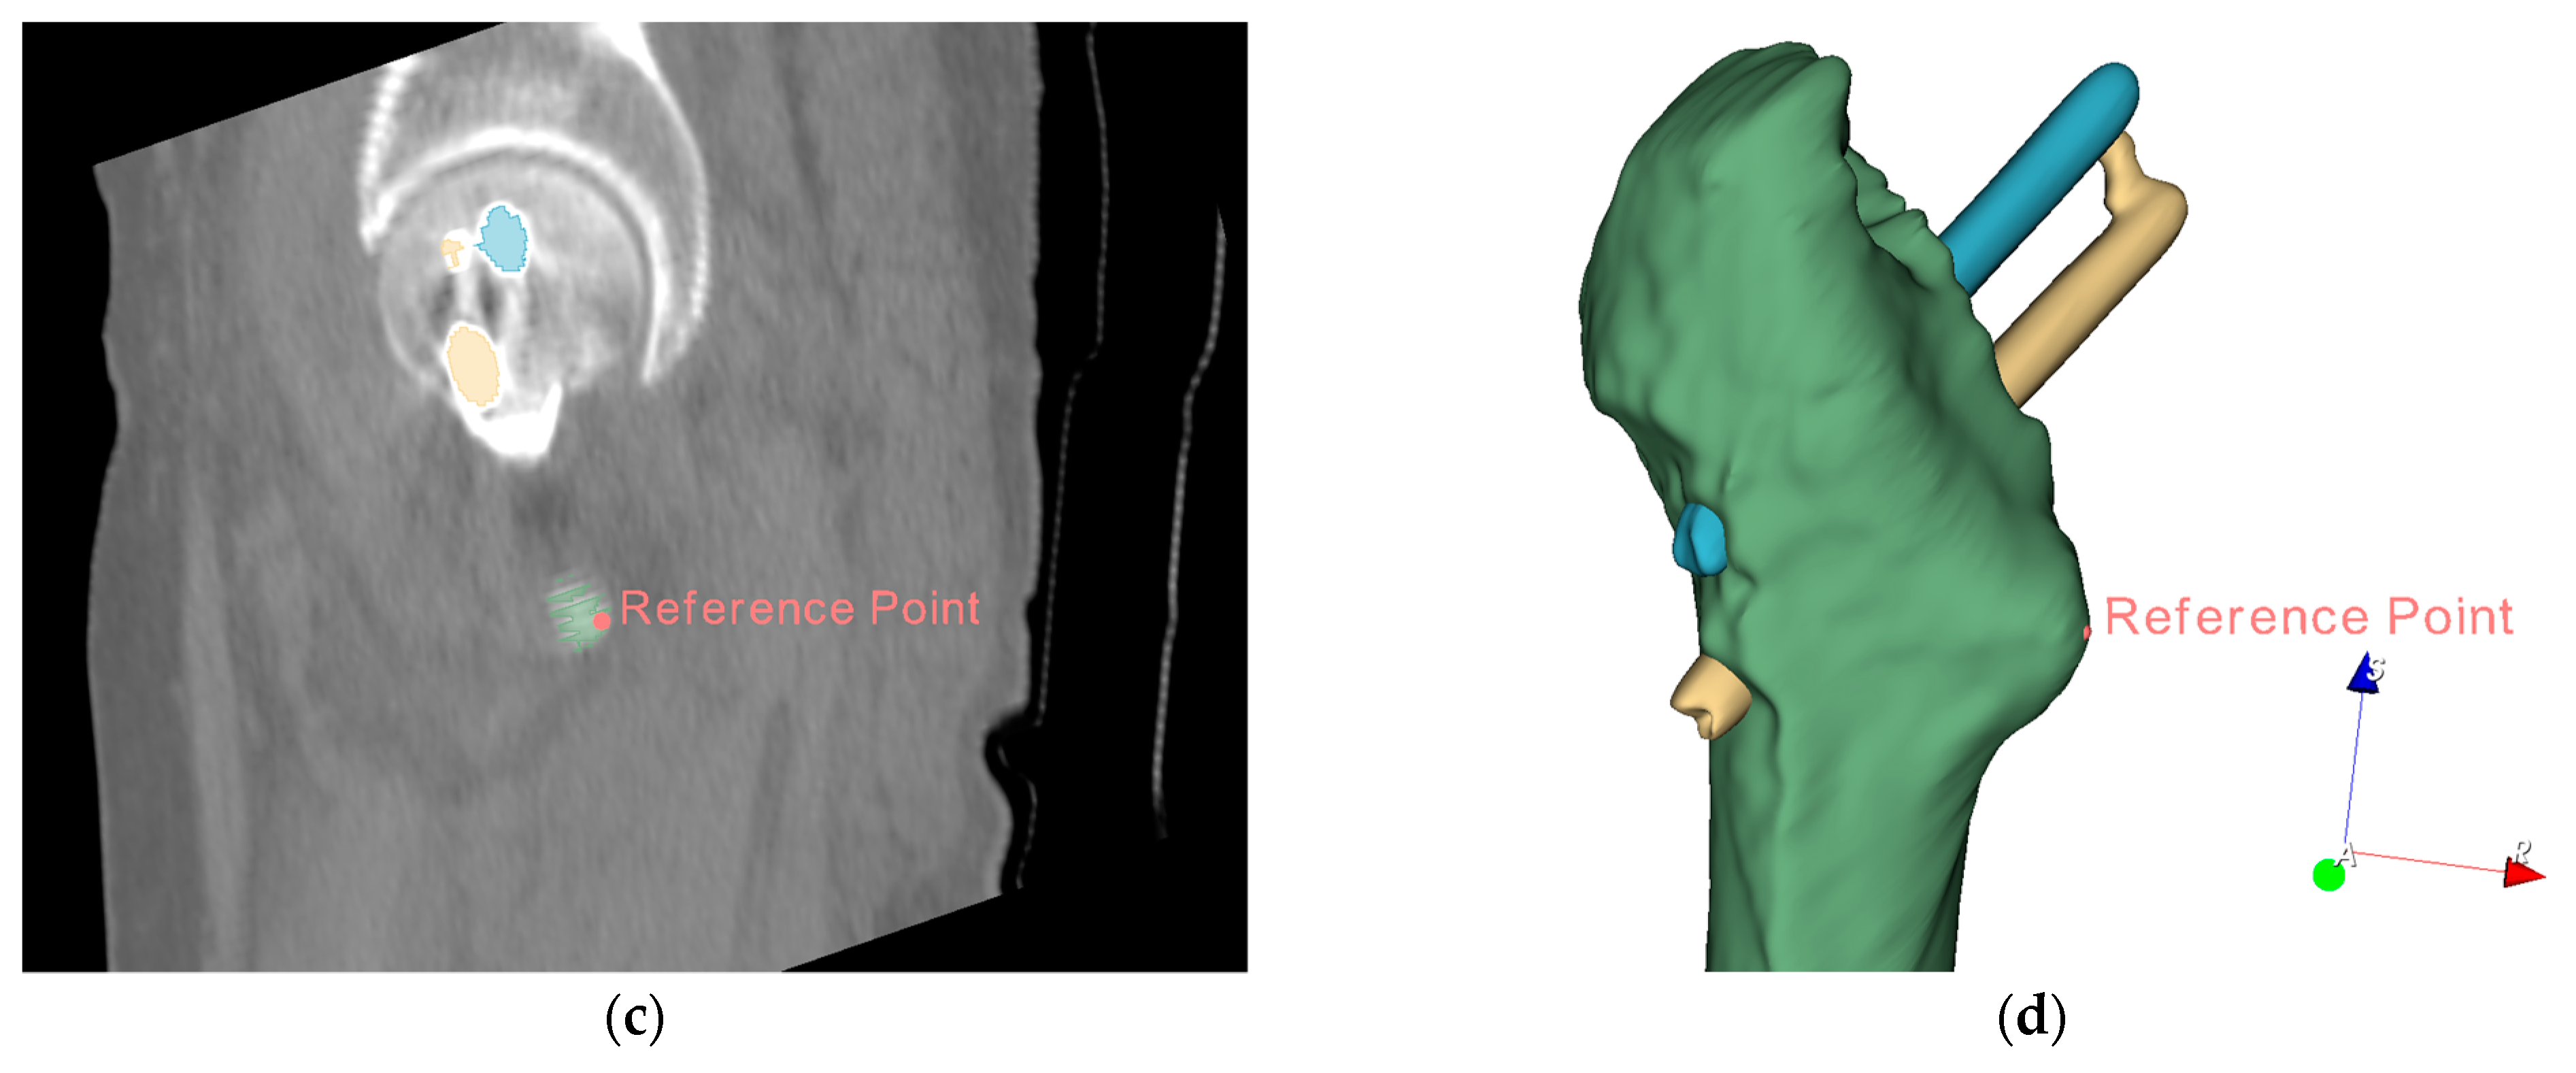

3.4. Measurement of Implant Displacement Based on Conventional Methods

In this subsection, to verify our proposed measurement of implant displacement’s validity, we used the reference point-based distance measurement method described in [18]. We define the point on the outer surface of the Lesser trochanter farthest from the centerline of the medullary cavity as reference point A. As shown in Figure 13a–c, all steps to locate point A were performed entirely using the three planes in the CT images, and no 3D femur model was used to assist in localization. Figure 13d is used to assist in showing the position of the reference point in the CT image.

Figure 13.

Locating reference point A in the CT image: (a) reference point located in the axial plane; (b) reference point located in the sagittal plane; (c) reference point located in coronal plane; (d) display reference point in the 3D model.

Point A is used as the origin, and a new coordinate system is formed with the intersecting lines of the planes, axial plane (green), coronal plane (blue), and sagittal plane (red), as shown in Figure 14. The coordinates of the target object are measured in the new coordinate system, and the Euclidean distance is calculated using the formula